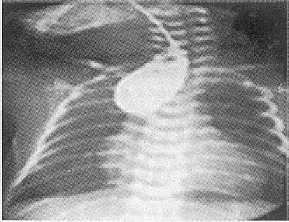

例1,男,34小时,因“气促,呻吟,口吐泡沫30小时”,以新生儿吸入性肺炎收住。其母孕3个月时曾感冒,未服药。体检:体重2300g,气促、口周发绀,口吐泡沫明显,双肺闻及中等大小湿音,心(-),腹稍膨隆。入院后经抗炎吸氧等对症处理后,患儿呼吸道分泌物多,洗胃时胃管不能插入胃内:疑食管闭锁、食管气管瘘。予行食管碘油造影胸腹X片检查,见盲端于第4胸椎,下端食管显影,自气管分叉至胃内可见一细条状透亮影,胃肠道内可见气体影像,未见上段食管内碘油向气管流入。X线诊断先天性食管闭锁并食管气管瘘(Ⅲ型),见图2。

图2 为生后38小时所拍